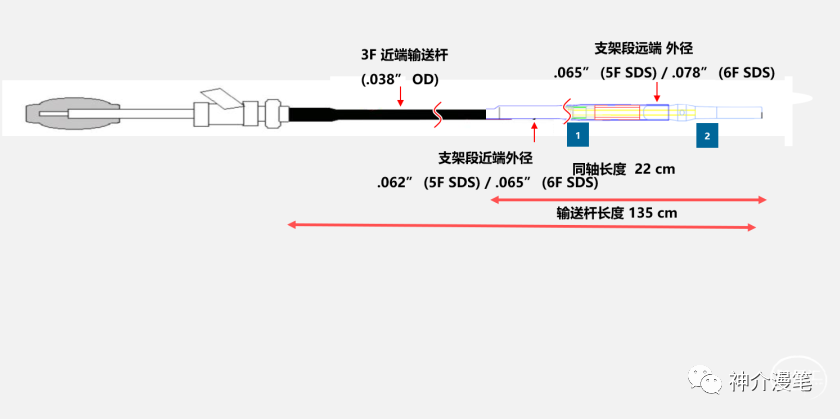

雅培上面两款支架一个开环,一个闭环,应用的场景,使用原则和上诉所说的支架大体差不多,大家可以再看一下他们的具体型号和尺寸。酌情使用,比较有意思的是这两款支架的释放都是“半自动化的”,支架到位后通过旋转释放手柄或回拉把手即可完成。不需要前面几款支架的推扒技术,所以一旦支架到位良好,释放极度简单,几乎就是傻瓜式释放,特别适合新手小白使用。

说一下雅培的Xpert支架吧,整体来说是个挺有想法的支架。号称复合设计,其实归根还是个开环支架,最大的特点是壁薄,外径小,可以经过更小的导管和鞘输送,对于迂曲通路这是一个好的设计。

3-6的支架可以使用4F鞘或6Fguiding进行释放,下图为其常见支架型号。